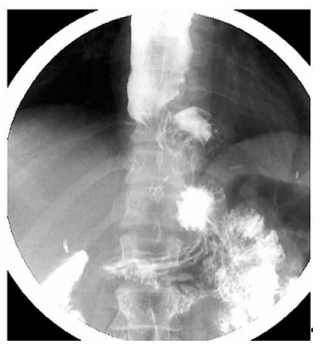

Paciente de 45 anos, submetido à miotomia de Heller

com fundoplicatura parcial (dor) por acalasia há oito meses, evoluiu com melhora inicial da disfagia, mas retornou com piora progressiva dos sintomas nos últimos dois

meses. A endoscopia digestiva alta mostrou esôfago dilatado com acúmulo de conteúdo alimentar e resistência

à passagem do aparelho na transição esofagogástrica. A

manometria esofágica de alta resolução não pôde ser realizada, pois não foi possível o posicionamento adequado do cateter manométrico na junção esofagogástrica.

Realizou o esofagograma apresentado a seguir:

Considerando a história e os achados do exame, qual é a conduta mais adequada?